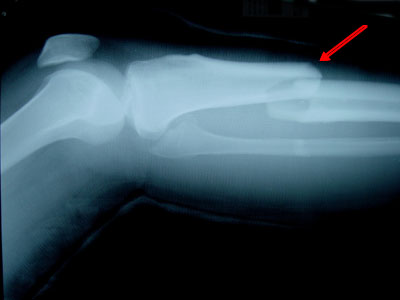

Tiến sĩ Tuấn và các cộng sự đã theo dõi và nghiên cứu dữ liệu của 822 người đàn ông ở tỉnh Dubbo (Úc) từ năm 1989 cho đến nay. Khi đó, những người này ở độ tuổi từ 60 trở lên. Sau đó, có 43 người bị ung thư tuyến tiền liệt, trong đó 22 người được điều trị bằng ADT, còn 21 người còn lại thì không dùng ADT. Kết quả là những người sử dụng ADT có nguy cơ gãy xương cao gấp 1,5 - 2 lần so với người không mắc bệnh ung thư này.

Tiến sĩ Tuấn giải thích: "Đàn ông bị ung thư tuyến tiền liệt thường có nồng độ kích thích tố androgen cao, tức có mật độ xương tốt, giúp giảm nguy cơ gãy xương. Nhưng không hẳn như thế, bởi vì những bệnh nhân này phải qua điều trị bằng ADT, cho nên họ thường bị mất xương khá nhanh, dẫn đến nguy cơ gãy xương cao".

Ông nhấn mạnh: "Nghiên cứu này có ý nghĩa quan trọng trong thực tiễn, vì kết quả cho thấy: thứ nhất, đa số đàn ông bị ung thư tuyến tiền liệt thường có mật độ chất khoáng trong xương (BMD) cao hơn; thứ hai, bệnh ung thư này rõ ràng làm tăng nguy cơ gãy xương; và thứ ba, việc điều trị bằng ADT đã làm tăng gấp đôi nguy cơ đó".